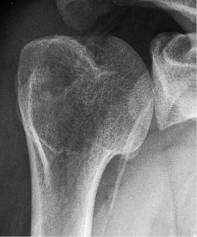

需要在肩关节内旋位、中立位、外旋位时分别拍摄3张正位X线,来评估有无Hill-Sachs损伤。

外旋位

如在肩关节外旋位的正位X线上能看到Hill-Sachs损伤,则评分应为2分;